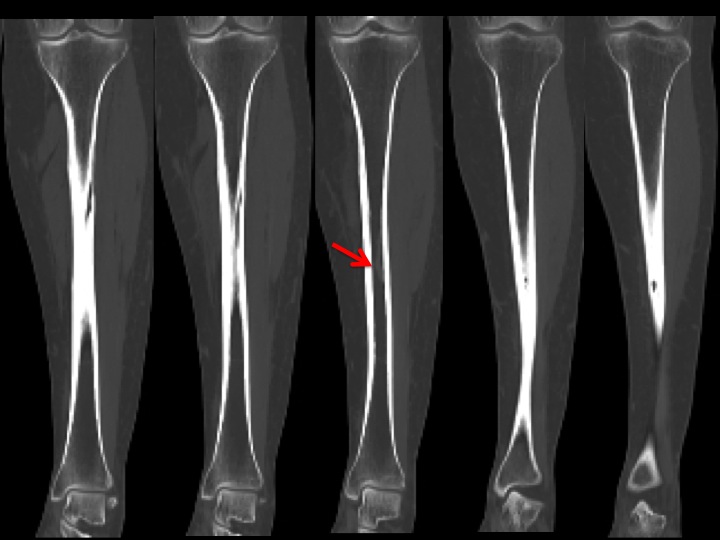

55F 4 days lower leg pain

XRs show a small lobulated intracortical lucency of the anterior tibial shaft which looks non aggressive. CT shows smooth, low attenuation defects in the posterior proximal tibial shaft and anterior medial distal shaft that are related to a varix, clearly seen in the ST windows, coursing through the bone into the pretibial soft tissues. I presume her pain was unrelated. This has been described long ago by Dr. Boutin. Had I read it, I could have skipped the CT. Reference article.

varix ( RID3366 )